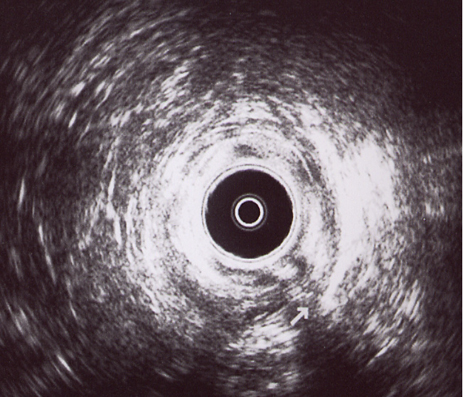

CANAL ANAL BAJO: Con agua oxigenada, trayecto que atraviesa esfínter externo subcuTáneo a las 5 h (flecha)